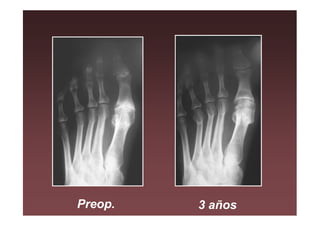

Preop.   3 años